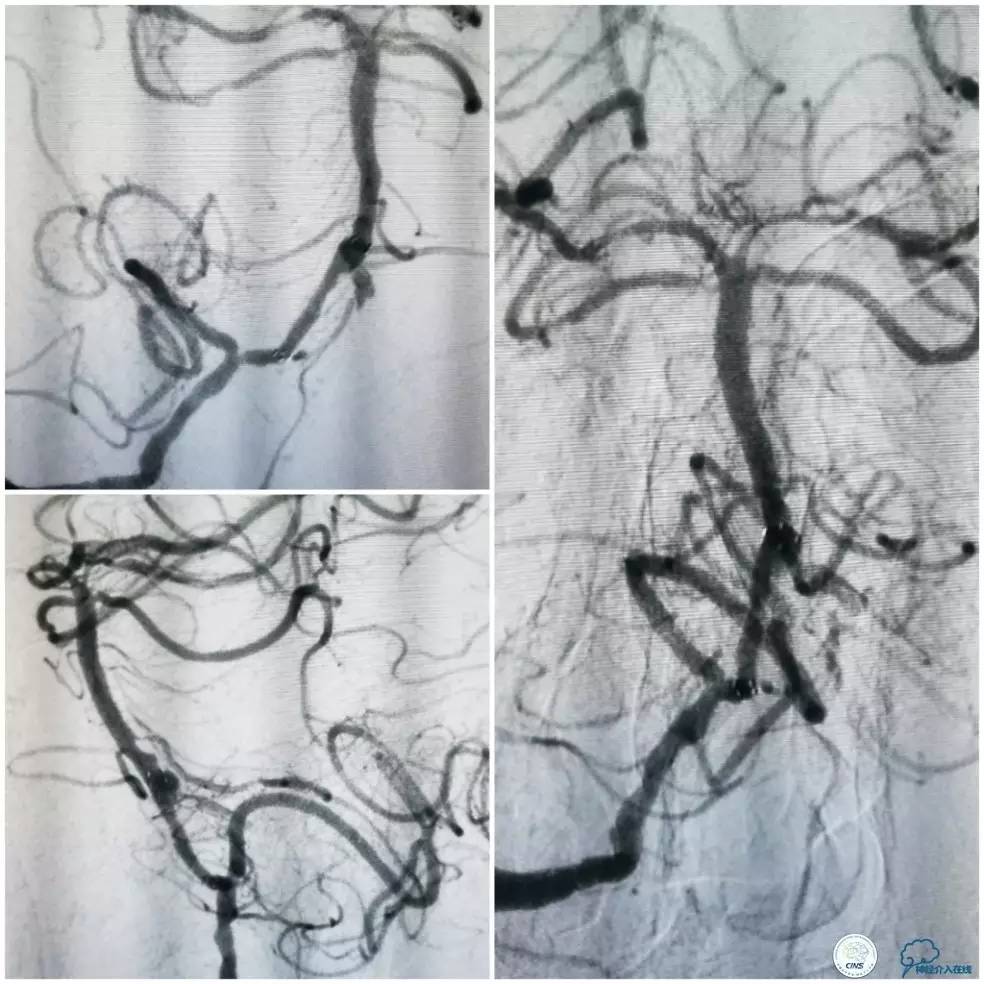

术前DSA:右椎动脉V1段长段重度狭窄,V4-基底动脉交界区显影浅淡,狭窄程度重,但具体程度显示欠佳(图7)。左椎动脉V1段闭塞,左椎动脉V2远段经侧支代偿显影,V3段以远未见显影(图8)。前循环造影未见明显前循环向后循环代偿(图9)。

图7

图8

图9

1. 患者右椎动脉优势,右椎动脉V1段长段重度狭窄、V4段-基底动脉重度狭窄(或者闭塞)。左椎动脉V1段闭塞,经侧支代偿的左椎动脉V3段以远未见显影亦考虑闭塞,拟处理右椎动脉。

2. 右椎动脉V1段狭窄程度重,病变长度长,但病变血管较为平直,估计先处理近端病变后导引导管越过支架难度不大,故决定先处理近端病变再处理远端病变。

3. 右椎动脉V4段-基底动脉长段狭窄,CT提示局部钙化明显,预计发生术中扩张困难的机率高,拟采用球囊预扩张,再放置自膨支架。